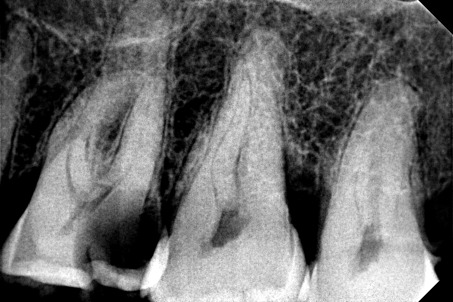

ΠΡΙΝ